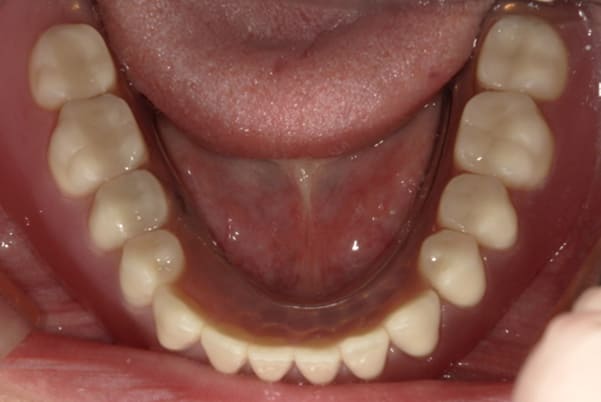

下顎治療後